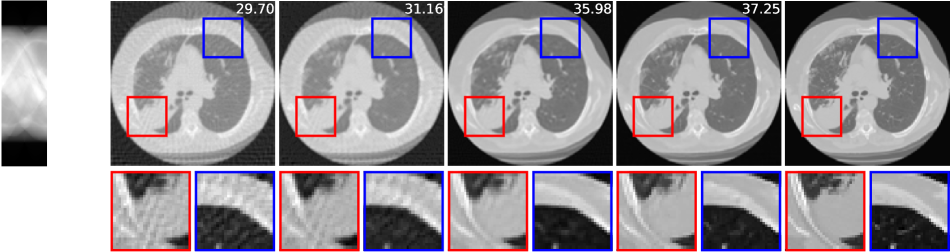

The imaging physics model of X-ray computed tomography (CT) is the discrete radon transform. The physics model is the radon transformation where 50 views (angles) are uniformly subsampled to generate the sparse-view sinograms (observations) . The Filtered back projection (FBP) function, i.e. iradon, is used to approximate . In this task, we exploit the invariance of the CT images to rotations222It is worth noting that shift invariance is not useful for the CT case, as the forward operator is shift invariant itself (see Corollary 1)., and is the group of rotations by degree (=360). We use the CT100 dataset [33], a public real CT clinic dataset which comprises 100 real in-vivo CT images collected from the cancer imaging archive333https://wiki.cancerimagingarchive.net/display/Public/TCGA-LUAD which consist of the middle slice of CT images taken from 69 different patients. The CT images are resized to pixels and we then apply the radon function on them to generate the -views sinograms. We used the first 90 sinograms for training while the remaining 10 sinograms for testing. Note in this task, the supervised trained residual U-Net is just the FBPConvNet proposed in [12] which has been demonstrated to be very effective in supervised learning for sparse-view CT image reconstruction. We train our model with equivariance strength (see SM for more results and the equivariance strength effect). using the sinograms alone while the FBPConvNet is trained with the ground truth pairs .

A qualitative comparison is presented in Figure 4. The sparse-view FBP contains the line artifacts. Both the FBPConvNet and our methods significantly reduce these artifacts, giving visually indistinguishable results. Figure 5 shows the value of PSNR of reconstruction on the training measurements and test measurements and we have the following observations: (i) We would naturally expect the network trained with ground truth data to perform the best. However, we note that the equivariant test error is almost as good despite having no access to ground truth images and only learning on the sparse sinogram data. Furthermore the EI solution is about 7 dB better than the FBP, clearly demonstrating the correct learning of the null space component of the image. (ii) We note that there is a significant gap between training and test error for the FBPConvNet, suggesting that the network may be overfitting. We do not observe this in the EI learning. This can be explained by the fact that the EI constrains the network to a much small class of functions (those that are equivariant on the data) and thus can be expected to have better generalization properties.

We also compared the EI with its adversarial extension in (7) and the supervised learning regularized by equivariance objective. The quantitative results are given in table 1 below. First, MC learning obtains a small improvement in performance over FBP which may be attributable to the fact that FBP is only an approximation to . Alternatively it may be due to the inductive bias of the neural network architecture [34]. Second, the adversarial extension provides a slight improvement to EI and similarly the EI regularization helps the vanilla supervised learning obtain a further 0.6 dB improvement. These results suggest that it is indeed possible to learn to reconstruct challenging inverse problems with only access to measurement data.

| FBP | MC | EI | Sup | |||

|---|---|---|---|---|---|---|

| 50-views CT | 30.24 | 31.01 | 36.94 | 36.96 | 38.17 | 38.79 |